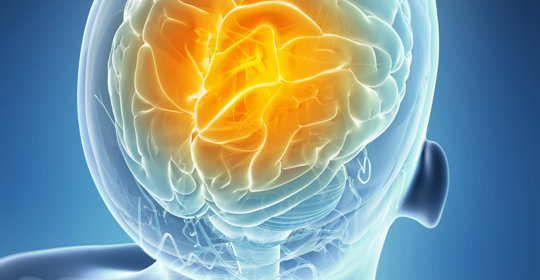

皮質膠質增生:中樞神經系統與肝臟健康

皮質膠質增生:年齡與神經細胞再生能力

腦下垂體腺瘤:症狀、診斷與治療